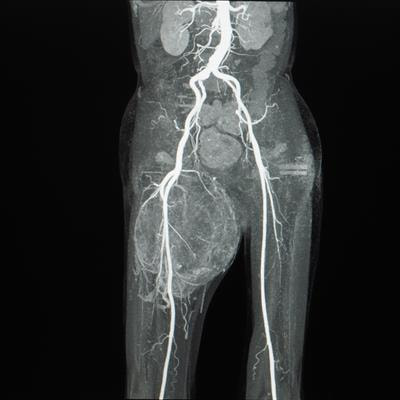

Retroperitoneal sarcoma is a mesenchymal tumor with strong heterogeneity. This Research Topic mainly explores how to improve the completion rate of resection by integrating insights from various major sarcoma institutions, proposing a comprehensive treatment strategy centered on surgery. It mainly explores the indications for simple surgery and expanded resection surgery, the changes in treatment methods brought by adjuvant therapy and neoadjuvant therapy, the feasibility of treatment plans guided by pathological types, the challenges posed by tumor invasion of blood vessels, and the treatment direction for patients who cannot undergo surgical resection.

6. Surgical management strategies for retroperitoneal sarcoma involving vascular invasion.